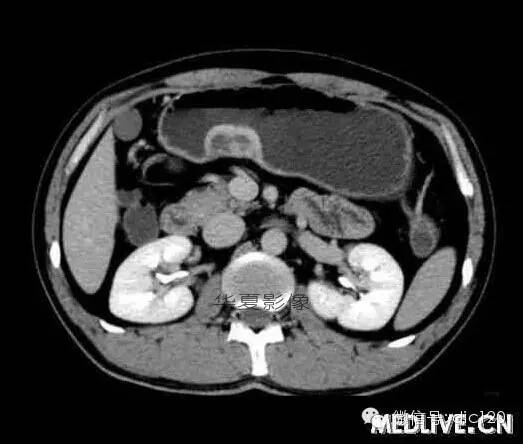

男,36歲,間斷性返酸噯氣3年,3個月前出現上腹疼痛,饑餓時加重。圖1-3為CT平掃,圖4-6分別為CT增強掃描的動脈期、門脈期和延遲期。

CT檢查可見胃幽門前區胃小彎側胃壁局限性增厚、隆起或伴凸向胃腔內的小結節灶,寬基地,境界光整,注射對比劑,增強掃描后,CT值可達50HU以上,與正常胰腺強化相仿。

胃迷走胰腺大多位在距幽門1-6cm的胃竇胃大彎側,粘膜下層內,為1-3cm大小的病灶。 與胃壁以寬基底相,增強掃描病灶表面覆蓋的黏膜明顯強化且連續,病灶內無明顯壞死,病變強化方式類似于正常胰腺組織;當病灶出現邊緣臍凹征或中央導管征時,對EP的診斷具有一定的特異性。